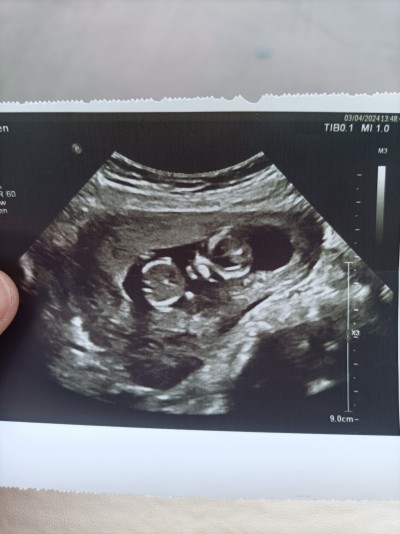

Merhabalar canlar 13 haftalık gebeyim doktor cinsiyet için bir ay sonra gel dedi resime bakabilir misiniz tahmin için çok merak ediyorum

Gebelik haftası 13

Buna göre erkek gibi geldi ama tabiki daha net fotograf olmasi gerekir cok belli olmuyor

Neresi kafa onu anlamadim bi kere ama pipi gorur gibi oldum :-D